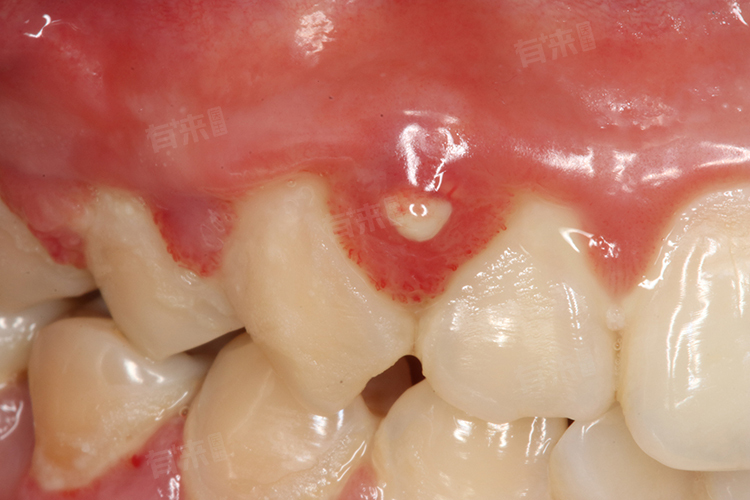

3、根尖周炎的瘘管表现:

- 当牙齿发生根尖周炎,炎症未得到及时控制,就可能在牙龈上形成瘘管,表现为白色小点。挤压时可能有脓液流出。这种情况需要对患牙进行根管治疗,医生通过清除根管内的感染物质,进行消毒、充填,消除根尖炎症,从根源上解决问题,随着炎症消退,牙龈上的白色点点及瘘管也会逐渐消失。